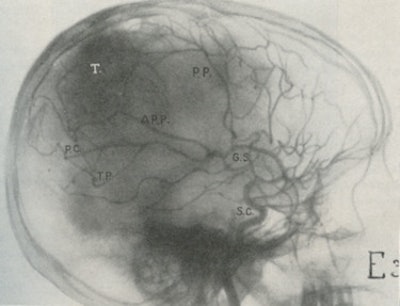

After these techniques failed, he tried using intra-arterial injections using an iodide salt. Moniz chose iodine because of its higher atomic weight compared with bromine. After many difficulties, he was successful using a 25% solution of sodium iodide with bilateral carotid artery cut downs. His successful patient, on 28 June 1927, was the ninth in his series, a young man with a pituitary tumor. In 1932, Moniz showed the head positioned for angiography (fig. 3) and angiogram (fig. 4) showing a tumor "T."

Fig. 4: Cerebral angiography (1932).